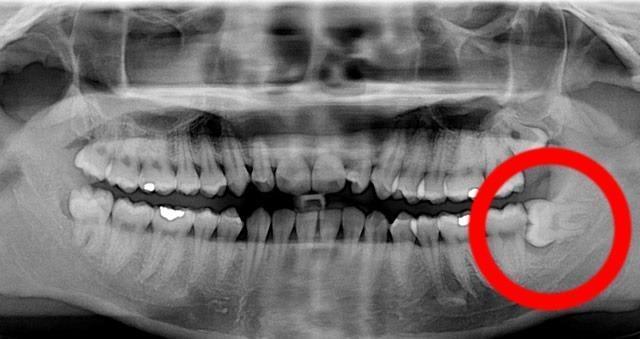

Os dentes do siso são chamados assim porque costumam doer desde que começam a sair, ao redor dos 16 anos, até que acabam de o fazer, às vezes até 10 anos depois. Devido à mudança da dieta dos humanos há uns 5000 anos atrás ou mais, existe uma tendência de um crescimento menor das mandíbulas, dificultando ainda mais o crescimento dos dentes, que muitas vezes devem ser extraídos já que amontoam para à frente (em 44% dos casos) ou não saem completamente pela gengiva (38% dos casos).

A extração dos dentes do siso pode ser realizada devido a vários fatores, mas é preciso observar sempre o impacto que teve ou pode ter em uma dentadura. O principal motivo é o desvio dos dentes anteriores, seguido de problemas de cáries devido à dificuldade gerada para escovar um dente sem ter saído completamente; é por isso que a extração sempre será objeto de uma profunda análise por parte do odontólogo. A extração dos dentes não costuma ser dolorosa, mas deve considerar alguns detalhes para não ter nenhuma surpresa. Neste artigo de umComo conhecerá mais sobre o assunto e sobre o cuidado da sua boca quando já tiver retirado o dente.